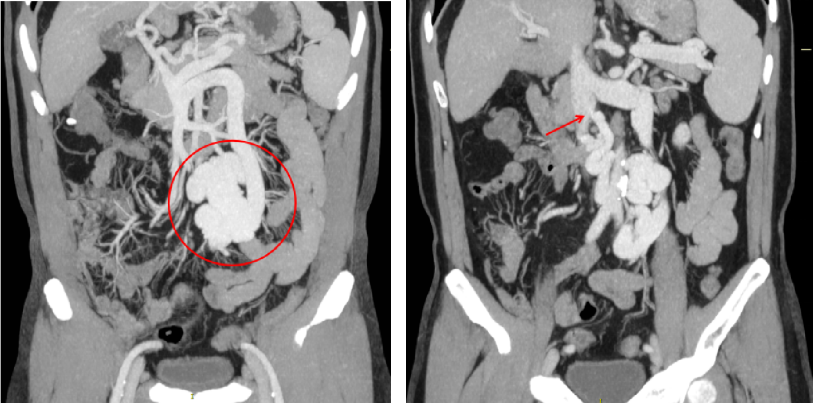

2023-07-25肝膽胰脾彩色多普勒:肝硬化,肝門靜脈纖細,血流反向,門靜脈高壓可能。膽囊壁稍粗增厚。脾稍大。腹腔未見明顯液性暗區(qū)。

2023-08-10 多排CT全腹部直接增強:肝硬化,脾大,門靜脈纖細,食管胃底靜脈曲張、異常分流道(腸系膜下靜脈-下腔靜脈分流,引流端近下腔靜脈腎靜脈分叉處)

2)腹部增強CT

異常分流道曲張靜脈較前顯著萎縮